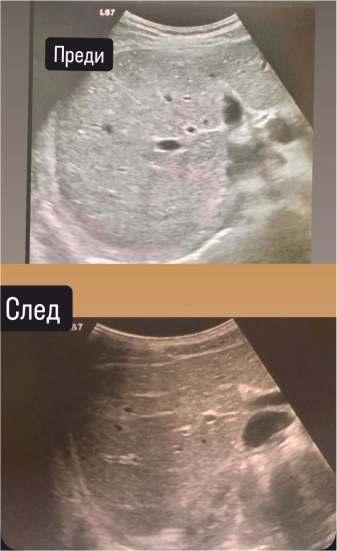

31–Всеки3-тиесомазненчерендроб!

35-Какдапреодолеемпредизвикателстватананеуспешнотоинвитро?